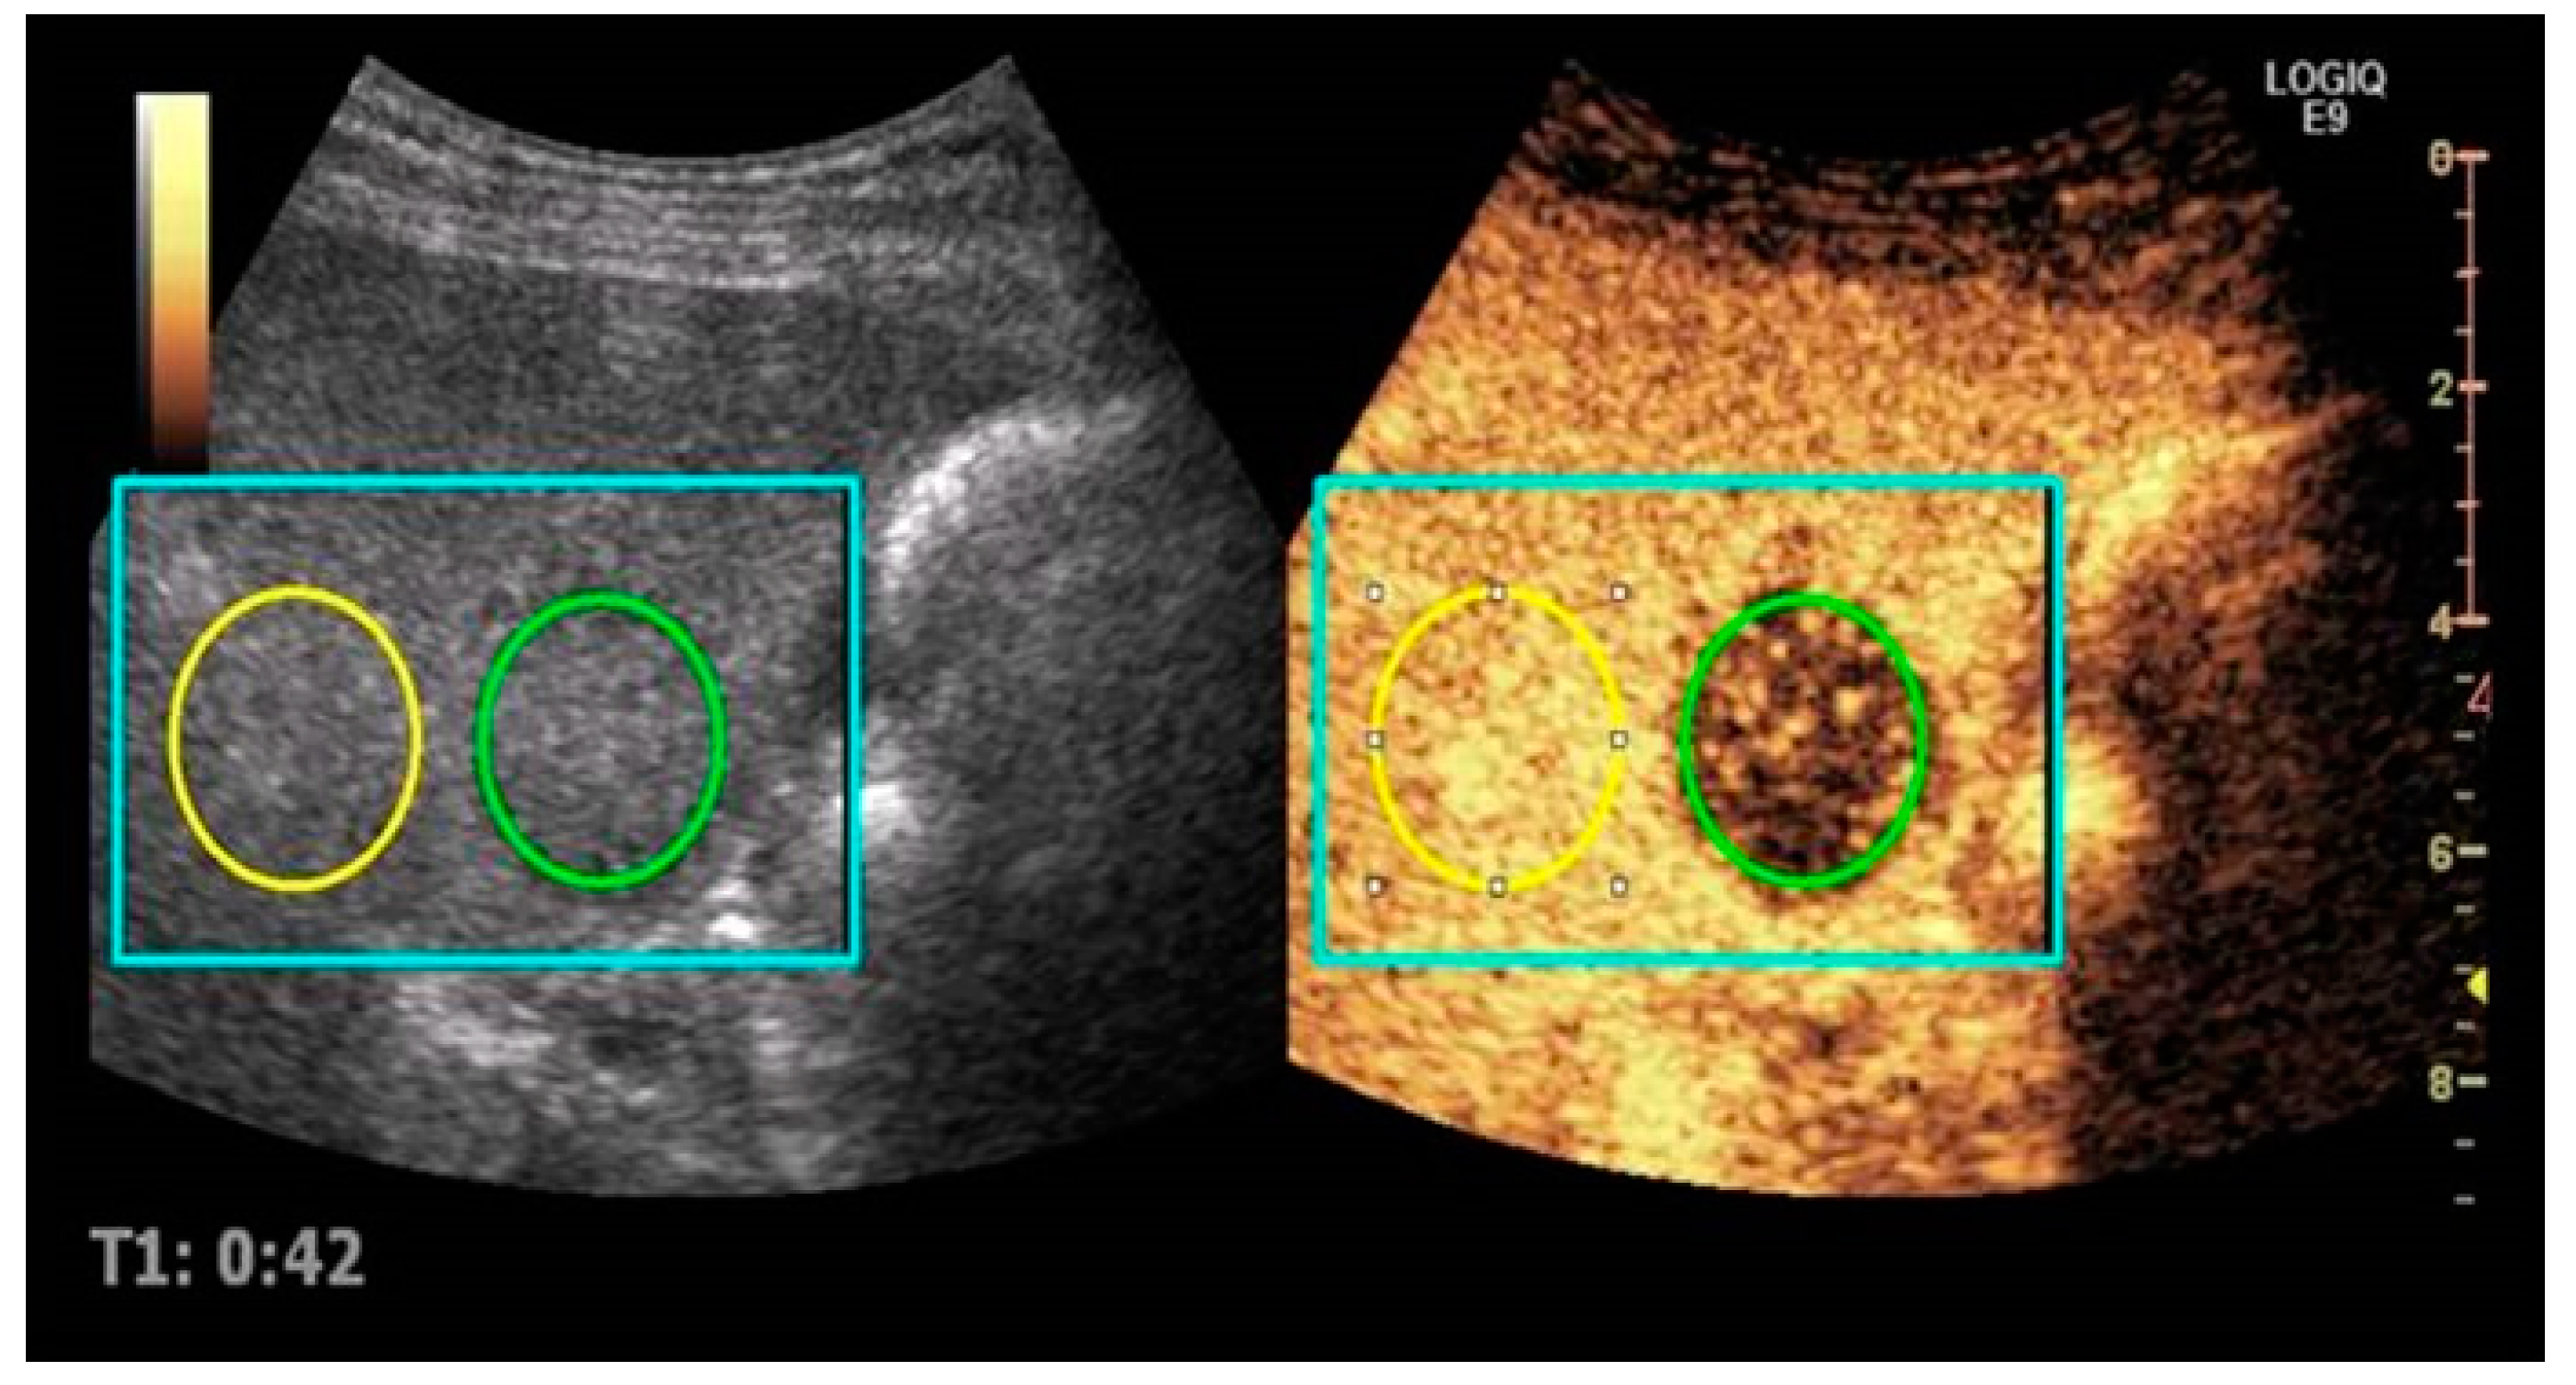

2.2. Imaging Protocol

2.3. Imaging Analysis